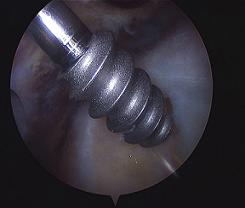

The picture on the top left shows, during shoulder arthroscopy surgery, a suture anchor being inserted into the bone of the head of the humerus, just next to the edge of the torn rotator cuff.